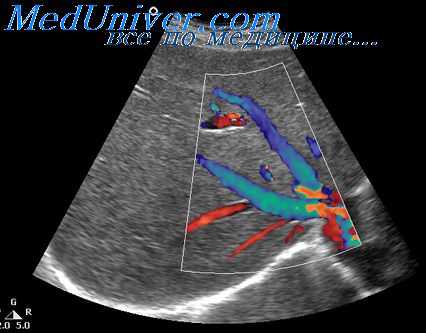

- Ультразвуковое исследование органов брюшной полости позволяет визуализировать структуру паренхимы, оценить размеры и топографию органа. Иногда дополнительно назначают ультразвуковую допплерографию селезенки, по результатам которой можно судить о кровоснабжении подозрительных узлов, скорости кровотока в селезеночных артериях, венах.